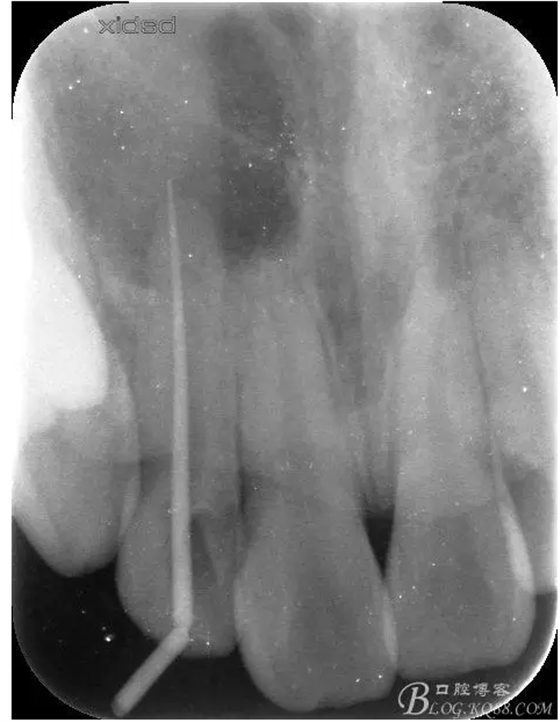

1.術前的根尖片檢查及根管治療影像: